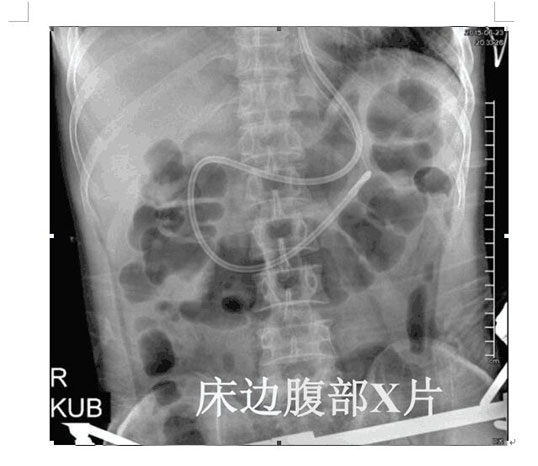

2017年4月22日,ICU成功開展了第一例床旁盲插經(jīng)鼻空腸管置入術(shù)并獲得成功。截止目前已為三位患者完成該術(shù),均為一次性盲插置管成功,臨床反映良好。此項(xiàng)技術(shù)的成功應(yīng)用,填補(bǔ)了我院在該護(hù)理技術(shù)領(lǐng)域的一項(xiàng)空白,標(biāo)志著ICU的護(hù)理技術(shù)水平邁上了一個(gè)新的臺(tái)階。

以往選擇在X線下或者使用胃鏡協(xié)助置入鼻空腸管,患者痛苦大且受輻射影響。而床旁徒手盲插經(jīng)鼻空腸管植入術(shù)是臨床護(hù)士在不依賴于其他輔助設(shè)備的情況下,通過一定的置管技巧,將管道插至十二指腸或空腸。此法省時(shí)、費(fèi)用低、操作方便、損傷小,尤其對胃蠕動(dòng)功能差的患者,不易引起食物反流、誤吸。鼻空腸管不僅可以從管內(nèi)注入營養(yǎng)液,而且還可以進(jìn)行胃腸減壓,值得臨床推廣。